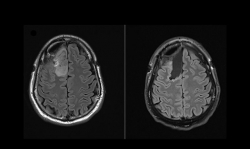

| Thử nghiệm lâm sàng lần đầu tiên trên thế giới về phương pháp điều trị u não Các nhà khoa học Australia vừa công bố một bước tiến quan trọng trong điều trị u não bằng cách lần đầu tiên sử dụng ... |